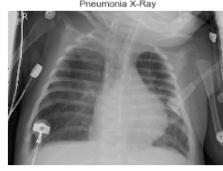

Fig-1:NormalCXRImages Fig-2:PneumoniaAffectedCXRImages